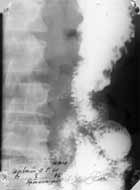

Моторно-эвакуаторная функция оперированного желудка и кишечника изучалась ретгенологическим методом, а также с помощью фотокамеры «Гранат 4». Средняя продолжительность полной эвакуации бариевой взвеси из культи желудка у больных с резецированным желудком по Ру с жомом составила 56,5+/-5,4 минут. При этом бариевая взвесь сразу же поступила в отводящую кишку, постепенно накапливаясь перед жомом в течение 2-3 минут, а затем, при открытии жома, малыми порциями поступала в дистальные отделы тонкой кишки. Какого-либо супрастенотического расширения участка кишки проксимальнее жома выявлено не было. Культя желудка имела воронкообразную форму с четкими контурами. С помощью фотокамеры установлено, что жом открывался лишь тогда, когда накапливалось определенное количество бариевой взвеси и культя желудка развивала достаточную мощность, чтобы преодолеть силу сокращения жома (Рисунок).

Рисунок. Больной С. Оперирован по Ру с жомом. В момент перистальтики жом смыкается (слева), при его раскрытии пища порциально поступает в кишку (справа).